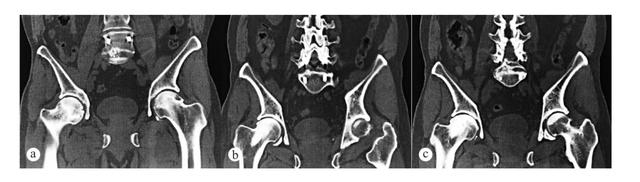

a为术前CT显示双侧股骨头缺血坏死,右侧严重,先行同种异体骨植入手术治疗;b和c为术后6、12个月分别复查CT显示右侧股骨头愈合良好 / [7]